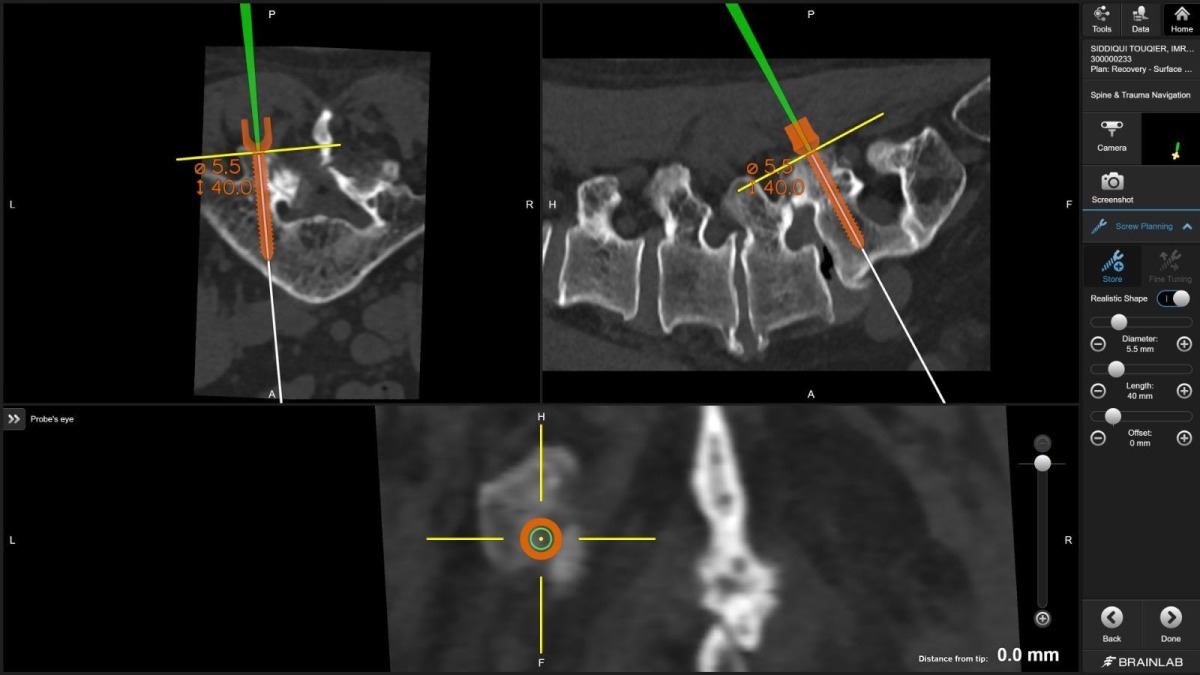

"For the first time in Qatar, I used virtual reality technology to plan spine screws before surgery," Dr. Belkhair explains. "These electronic glasses showed me 3D images of the patient's CT scan, allowing me to plan screw placement in the perfect position. What I saw in those glasses translated directly into the operating room, visible on screens, guiding every movement."

Navigated spine surgery combines real-time, three-dimensional imaging with optical or electromagnetic tracking systems that follow surgical instruments as they move through the body. Think of it as GPS for the human spine, mapping instruments within the vertebral anatomy with millimeter-level accuracy.

Dr. Belkhair took this further. Before the patient entered the operating room, he used virtual reality glasses that transformed CT scan data into an immersive, three-dimensional surgical rehearsal space. He could rotate the spine, zoom into pedicles (the narrow bone corridors where screws must pass), measure angles, and plan screw trajectories with unprecedented detail.

"The planning became the roadmap. The navigation ensured we followed it perfectly," he notes.

Dr. Belkhair's integration of VR planning with intraoperative navigation creates a seamless workflow: plan in virtual space, execute with real-time guidance, verify with immediate imaging.

"The glasses showed me the patient's spine as if I could hold it in my hands," Dr. Belkhair describes. "I could see where every screw needed to go, what angle, what depth. It's surgical precision at a level we couldn't achieve even five years ago."